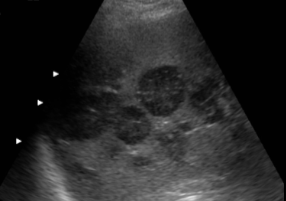

pyogenic abscess

ameobic abscess